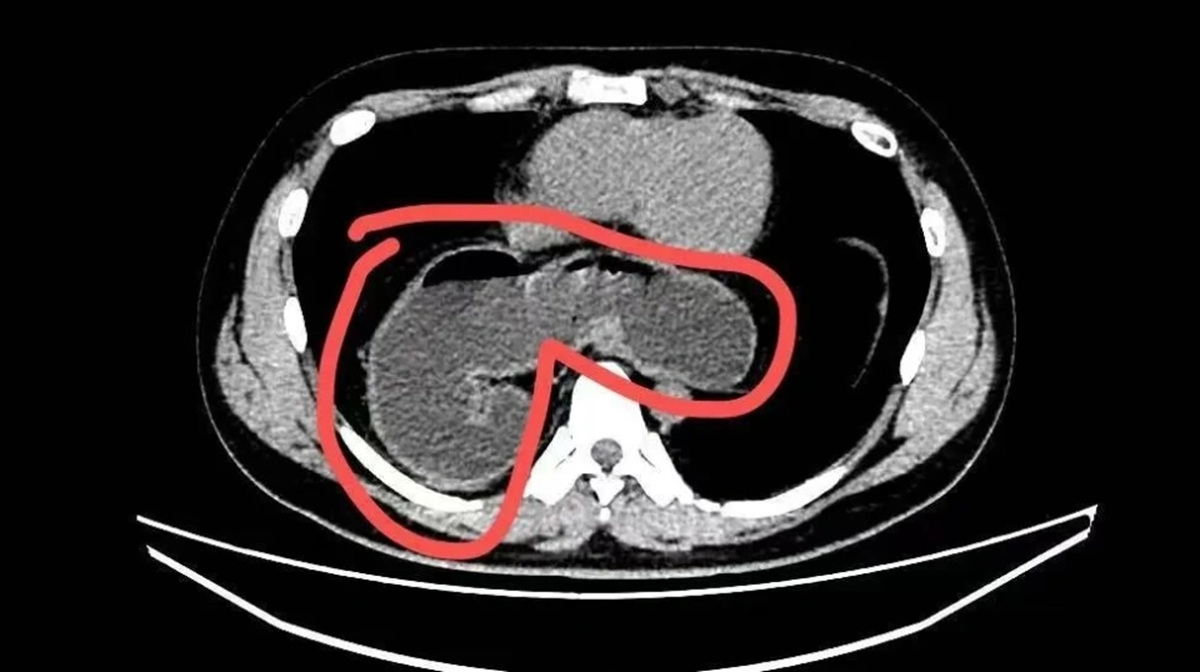

Mãi đến tháng 10 năm ngoái, do ho kéo dài kèm viêm phổi dai dẳng không khỏi, anh được chụp CT phổi. Kết quả khiến cả bệnh nhân lẫn gia đình sững sờ: một phần dạ dày đã “chạy” qua lỗ thực quản lên lồng ngực . Nội soi sau đó xác định anh mắc thoát vị khe thực quản kèm viêm thực quản trào ngược và xoắn dạ dày. Rất may, anh được phẫu thuật xâm lấn tối thiểu và xuất viện chỉ sau 3 ngày.

Theo bác sĩ, thoát vị khe thực quản xảy ra khi lỗ tự nhiên trên cơ hoành - nơi thực quản đi từ ngực xuống bụng - bị giãn rộng bất thường. Khi “cánh cửa” này lỏng ra, dạ dày, thậm chí cả ruột hoặc lách, có thể bị đẩy ngược lên khoang ngực. Hệ quả là axit dạ dày dễ trào ngược gây nóng rát, ợ chua, khó nuốt, đau ngực; nặng hơn có thể dẫn đến xoắn dạ dày, tắc nghẽn, không ăn uống được.